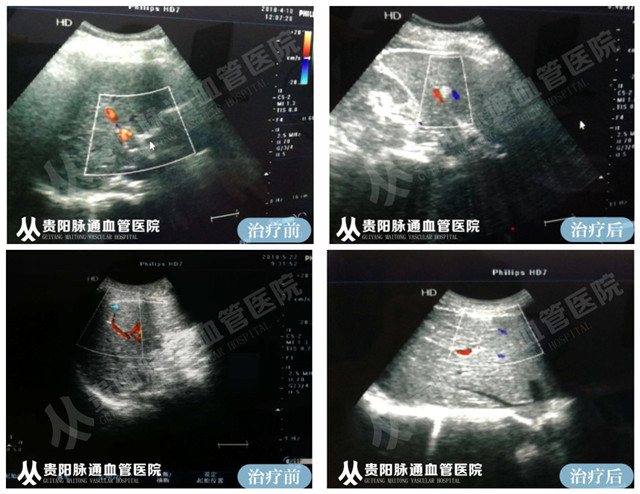

案例分享: